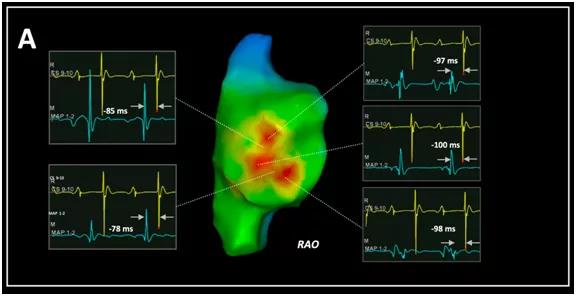

典型心房激动顺序如下图所示,该患者右心房游离壁可见三个EAS,领先CS 9~10 A波97~100 ms,而在中间区域的激动时间较EAS延迟≥10 ms。而传统多旁路的激动仅沿单一旁路逆传,故激动图表现为单个"突破点",仅在其中一处逆传功能被阻断后,才表现为另一条分支传导,并伴随着逆传激动顺序和体表预激形态的改变。

基于上述标准,我们在此类患者中平均可标测到3(IQR 2~4)个EAS,分布在左前斜位下7~11点钟方向,且均位于远离三尖瓣环的右房游离壁区域,距三尖瓣环平均最远距离22.6 mm,最近距离15.9 mm,EAS间最远距离平均相距22.9 mm,其中78.9%的患者可在心动过速时的EAS局部记录到QS型的单极电图。